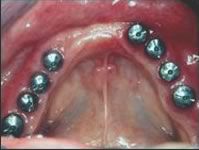

Nous vous proposons des réalisations scéllées, transvissées, transvissées-collées, unitaire ou en bridge, que ce soit tout céramique :

ou en céramo-métallique :